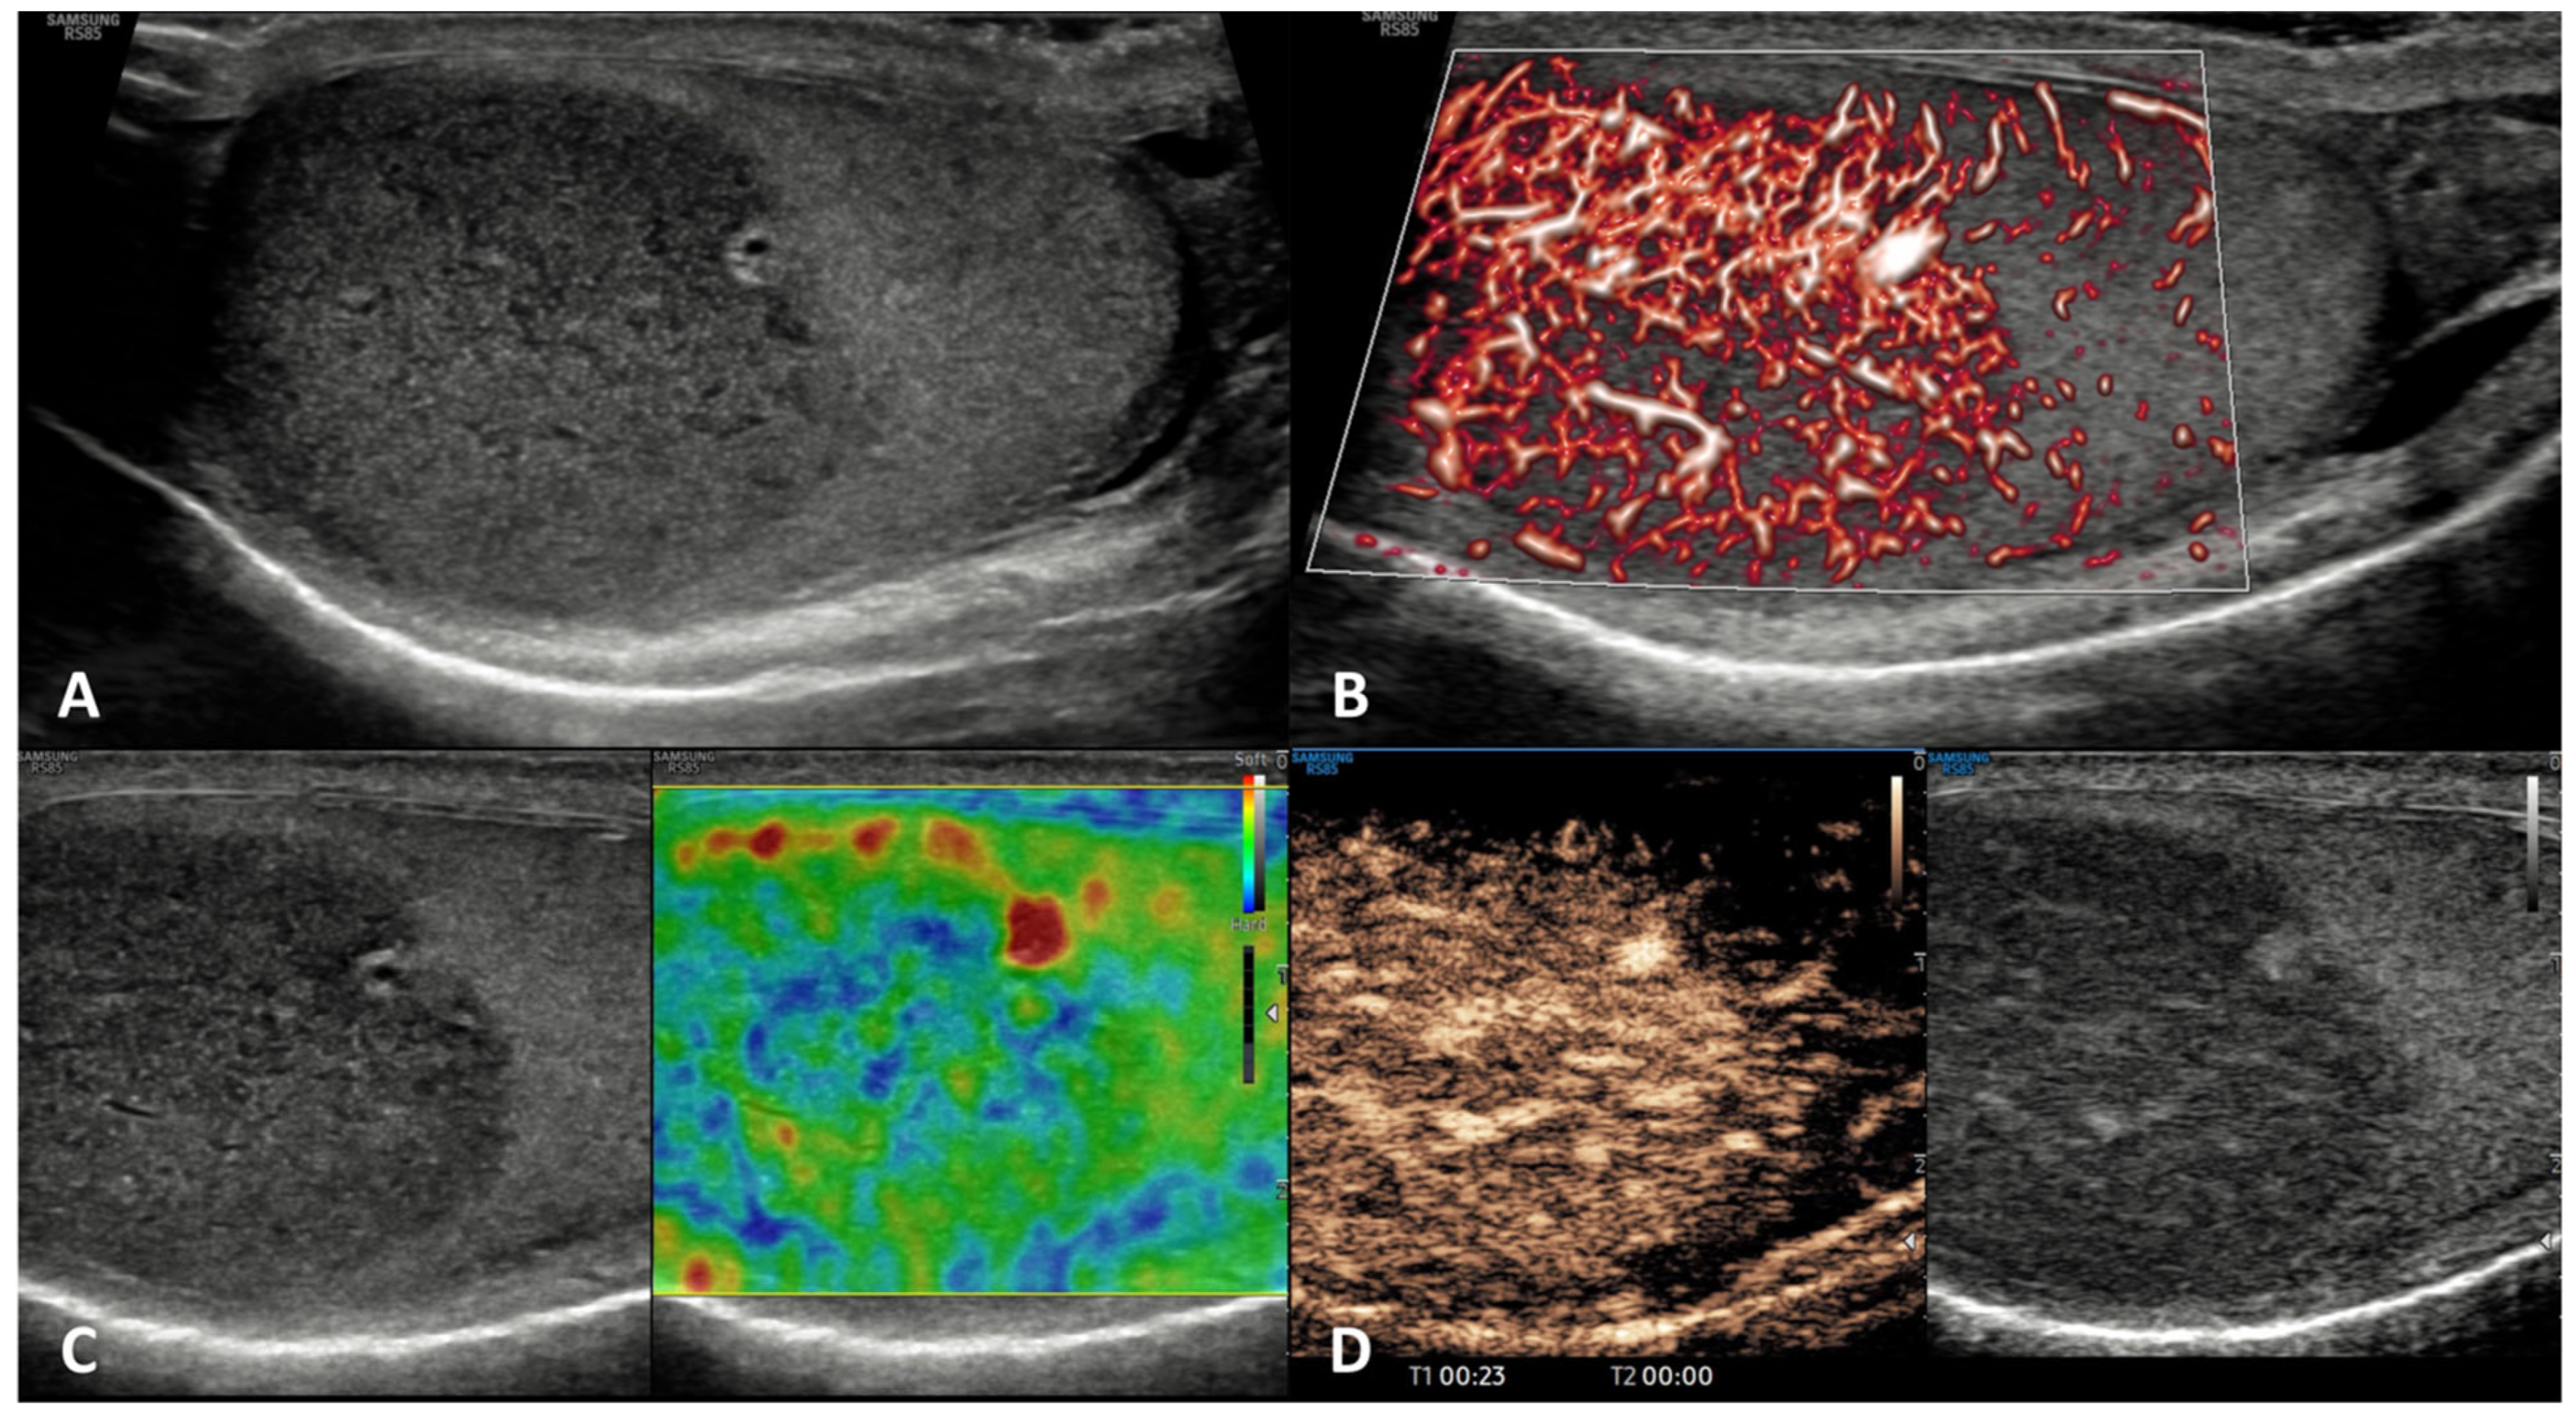

| Seminoma | Testicular swelling, pain, lumbar pain OR asymptomatic palpable firm testicular mass; possible gynecomastia | possible increase of β-hCG | Hypoechoic homogeneous round or oval lesion, occasionally multinodular or with polycyclic lobulated margins (unfrequently inhomogeneous) | Hypervascularized, with arborization and branches | Homogeneously hyperenhanced (rapid wash-in and wash-out) | Hard lesions with low/absent elastic strain |